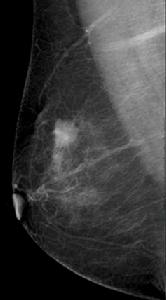

圖1 右側乳腺內外側斜位片 右側乳腺上象限分葉狀高密度結節,邊緣有毛刺,提示高度可疑惡性病灶。術後病理:乳腺癌。